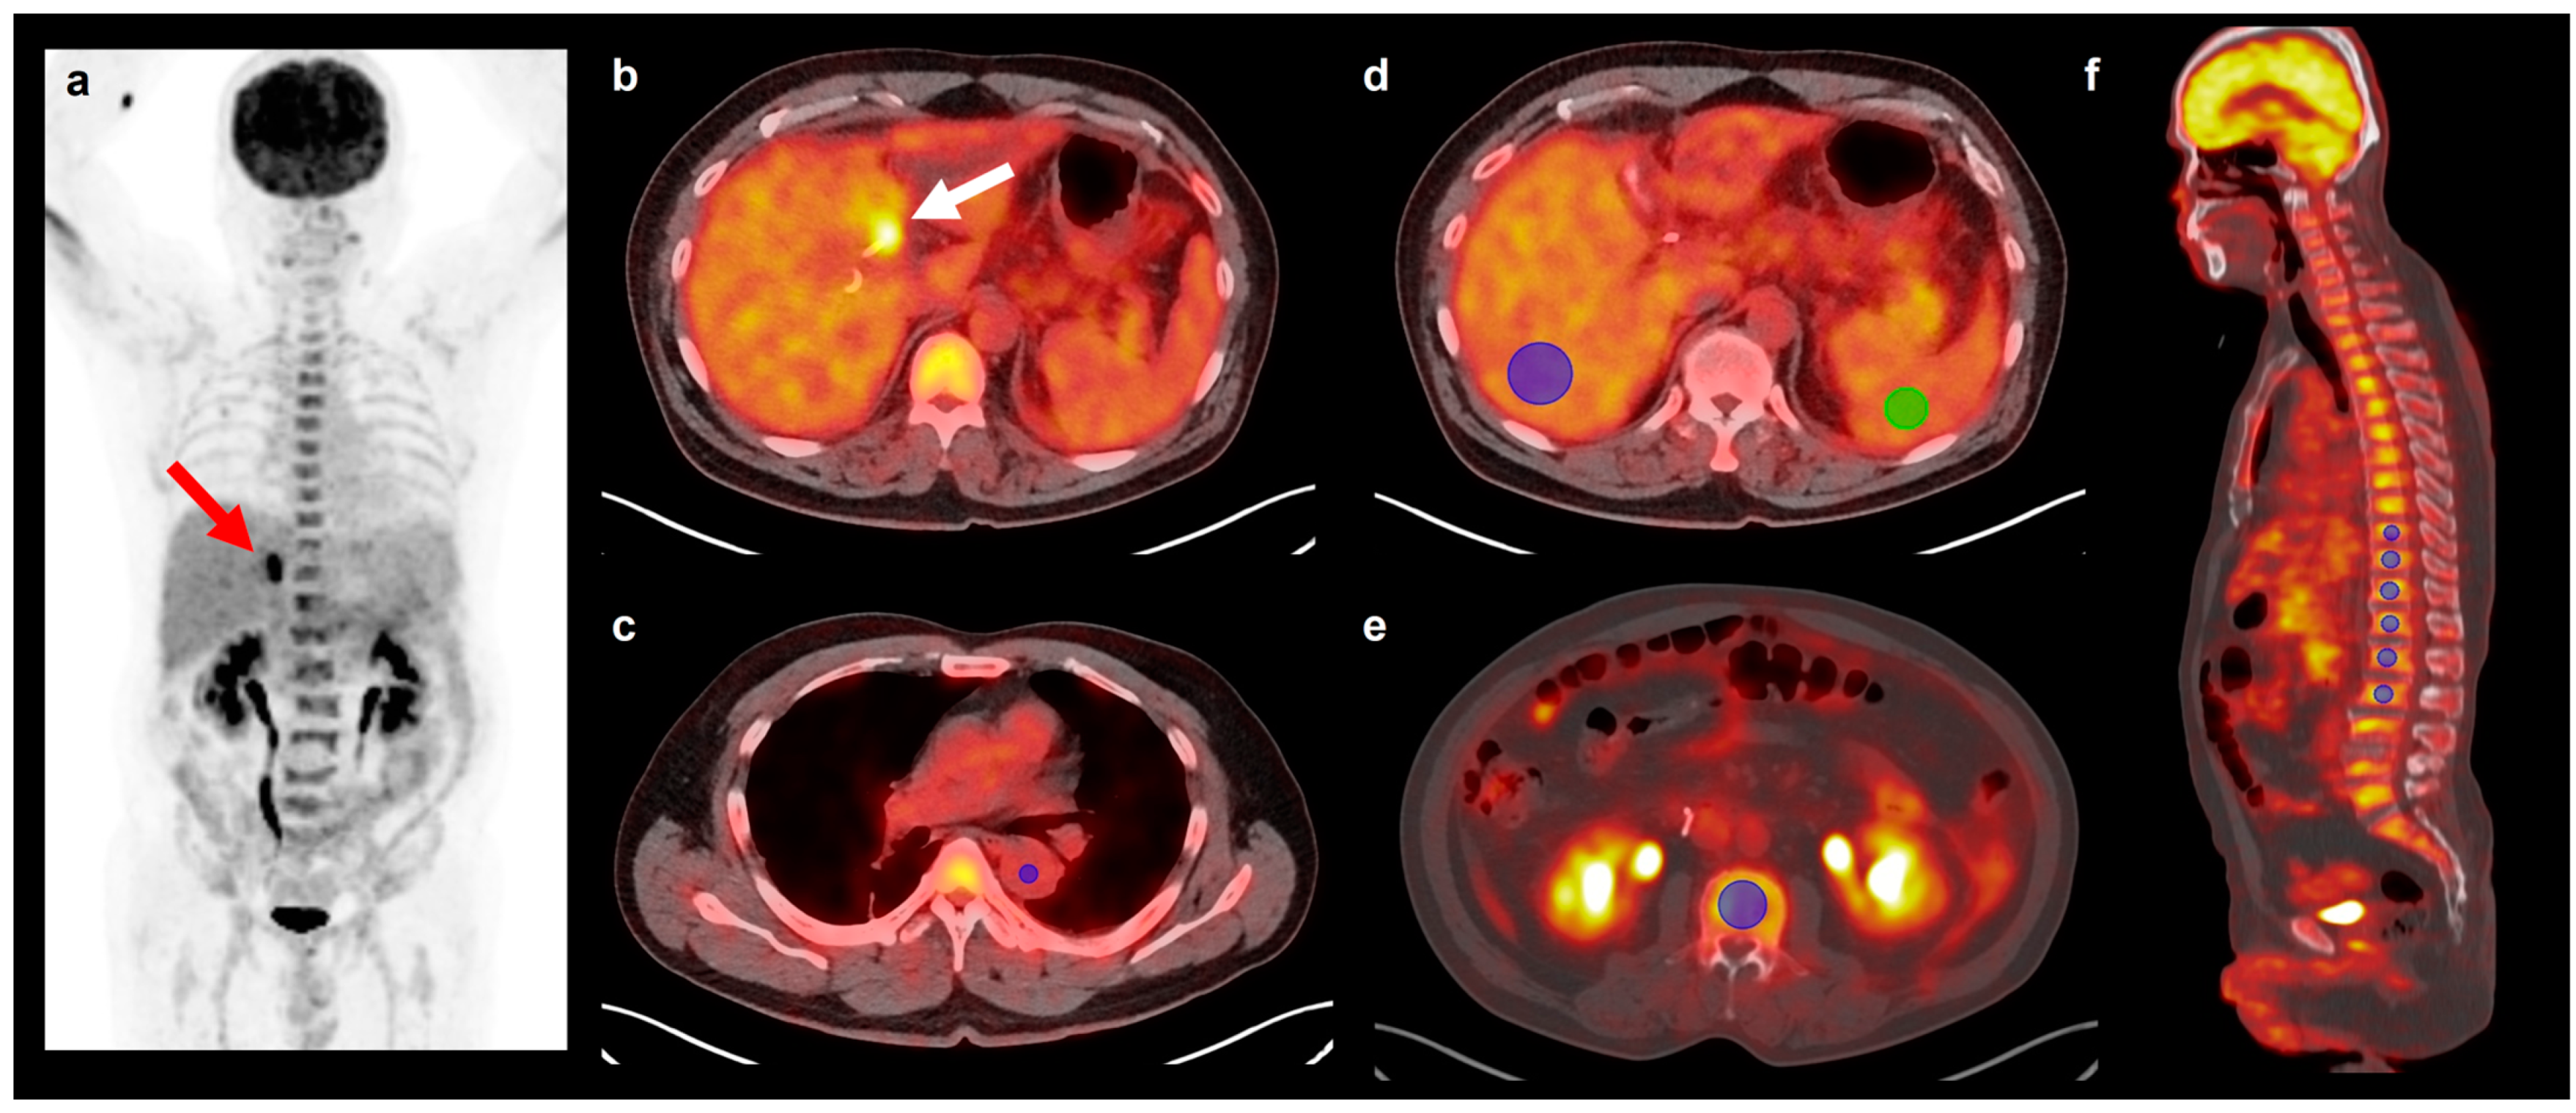

2.2. Measurement of FDG PET/CT Parameters